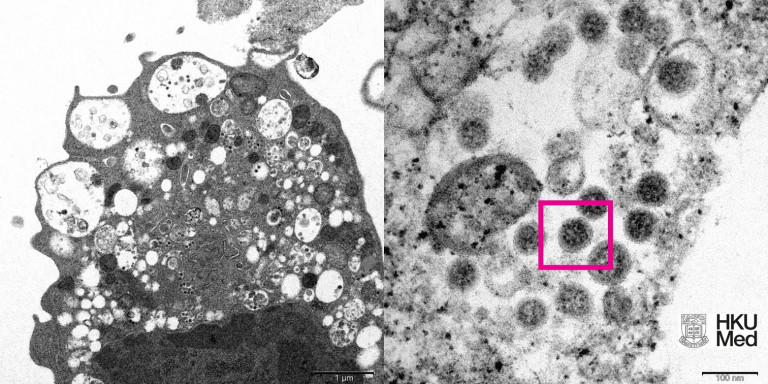

Οι ερευνητές κατάφεραν να απομονώσουν την «Όμικρον» από κλινικά δείγματα, κάτι που θα επιτρέψει την ανάπτυξη και την παραγωγή εμβολίων κατά της νέας παραλλαγής.